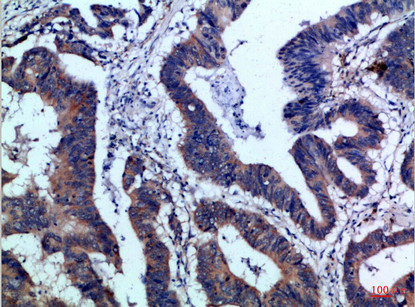

Immunohistochemical analysis of paraffin-embedded Human-colon-cancer, antibody was diluted at 1:100